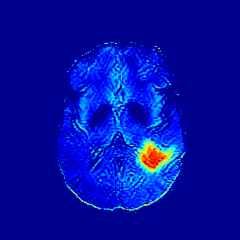

We observe that the generated normal-looking from ANT-GAN can also be used to directly segment the image, since the only difference between a synthesized normal-looking image and its real abnormal counterpart is region with the lesion. To illustrate this, we calculate the absolute difference between x𝑥x and 𝒢A2N(x)subscript𝒢A2N𝑥\mathcal{G}_{\rm{A2N}}(x) and show the segmentation after binary thresholding at 0.1 in Figure 9.

Refer to caption

(a) Tumor x𝑥x

(b) 𝒢A2N(x)subscript𝒢A2N𝑥\mathcal{G}_{\rm{A2N}}(x)

(c) Prediction

(d) Label

Figure 9: Example segmentation obtained by taking the absolute difference between the real tumor MRI x𝑥x and the generated normal-looking MRI 𝒢A2N(x)subscript𝒢A2N𝑥\mathcal{G}_{\rm{A2N}}(x), after binarization at a preset threshold.